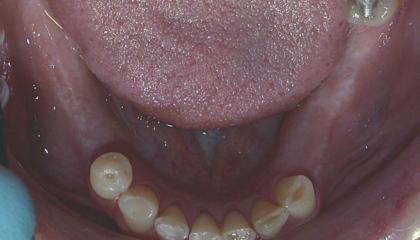

Before